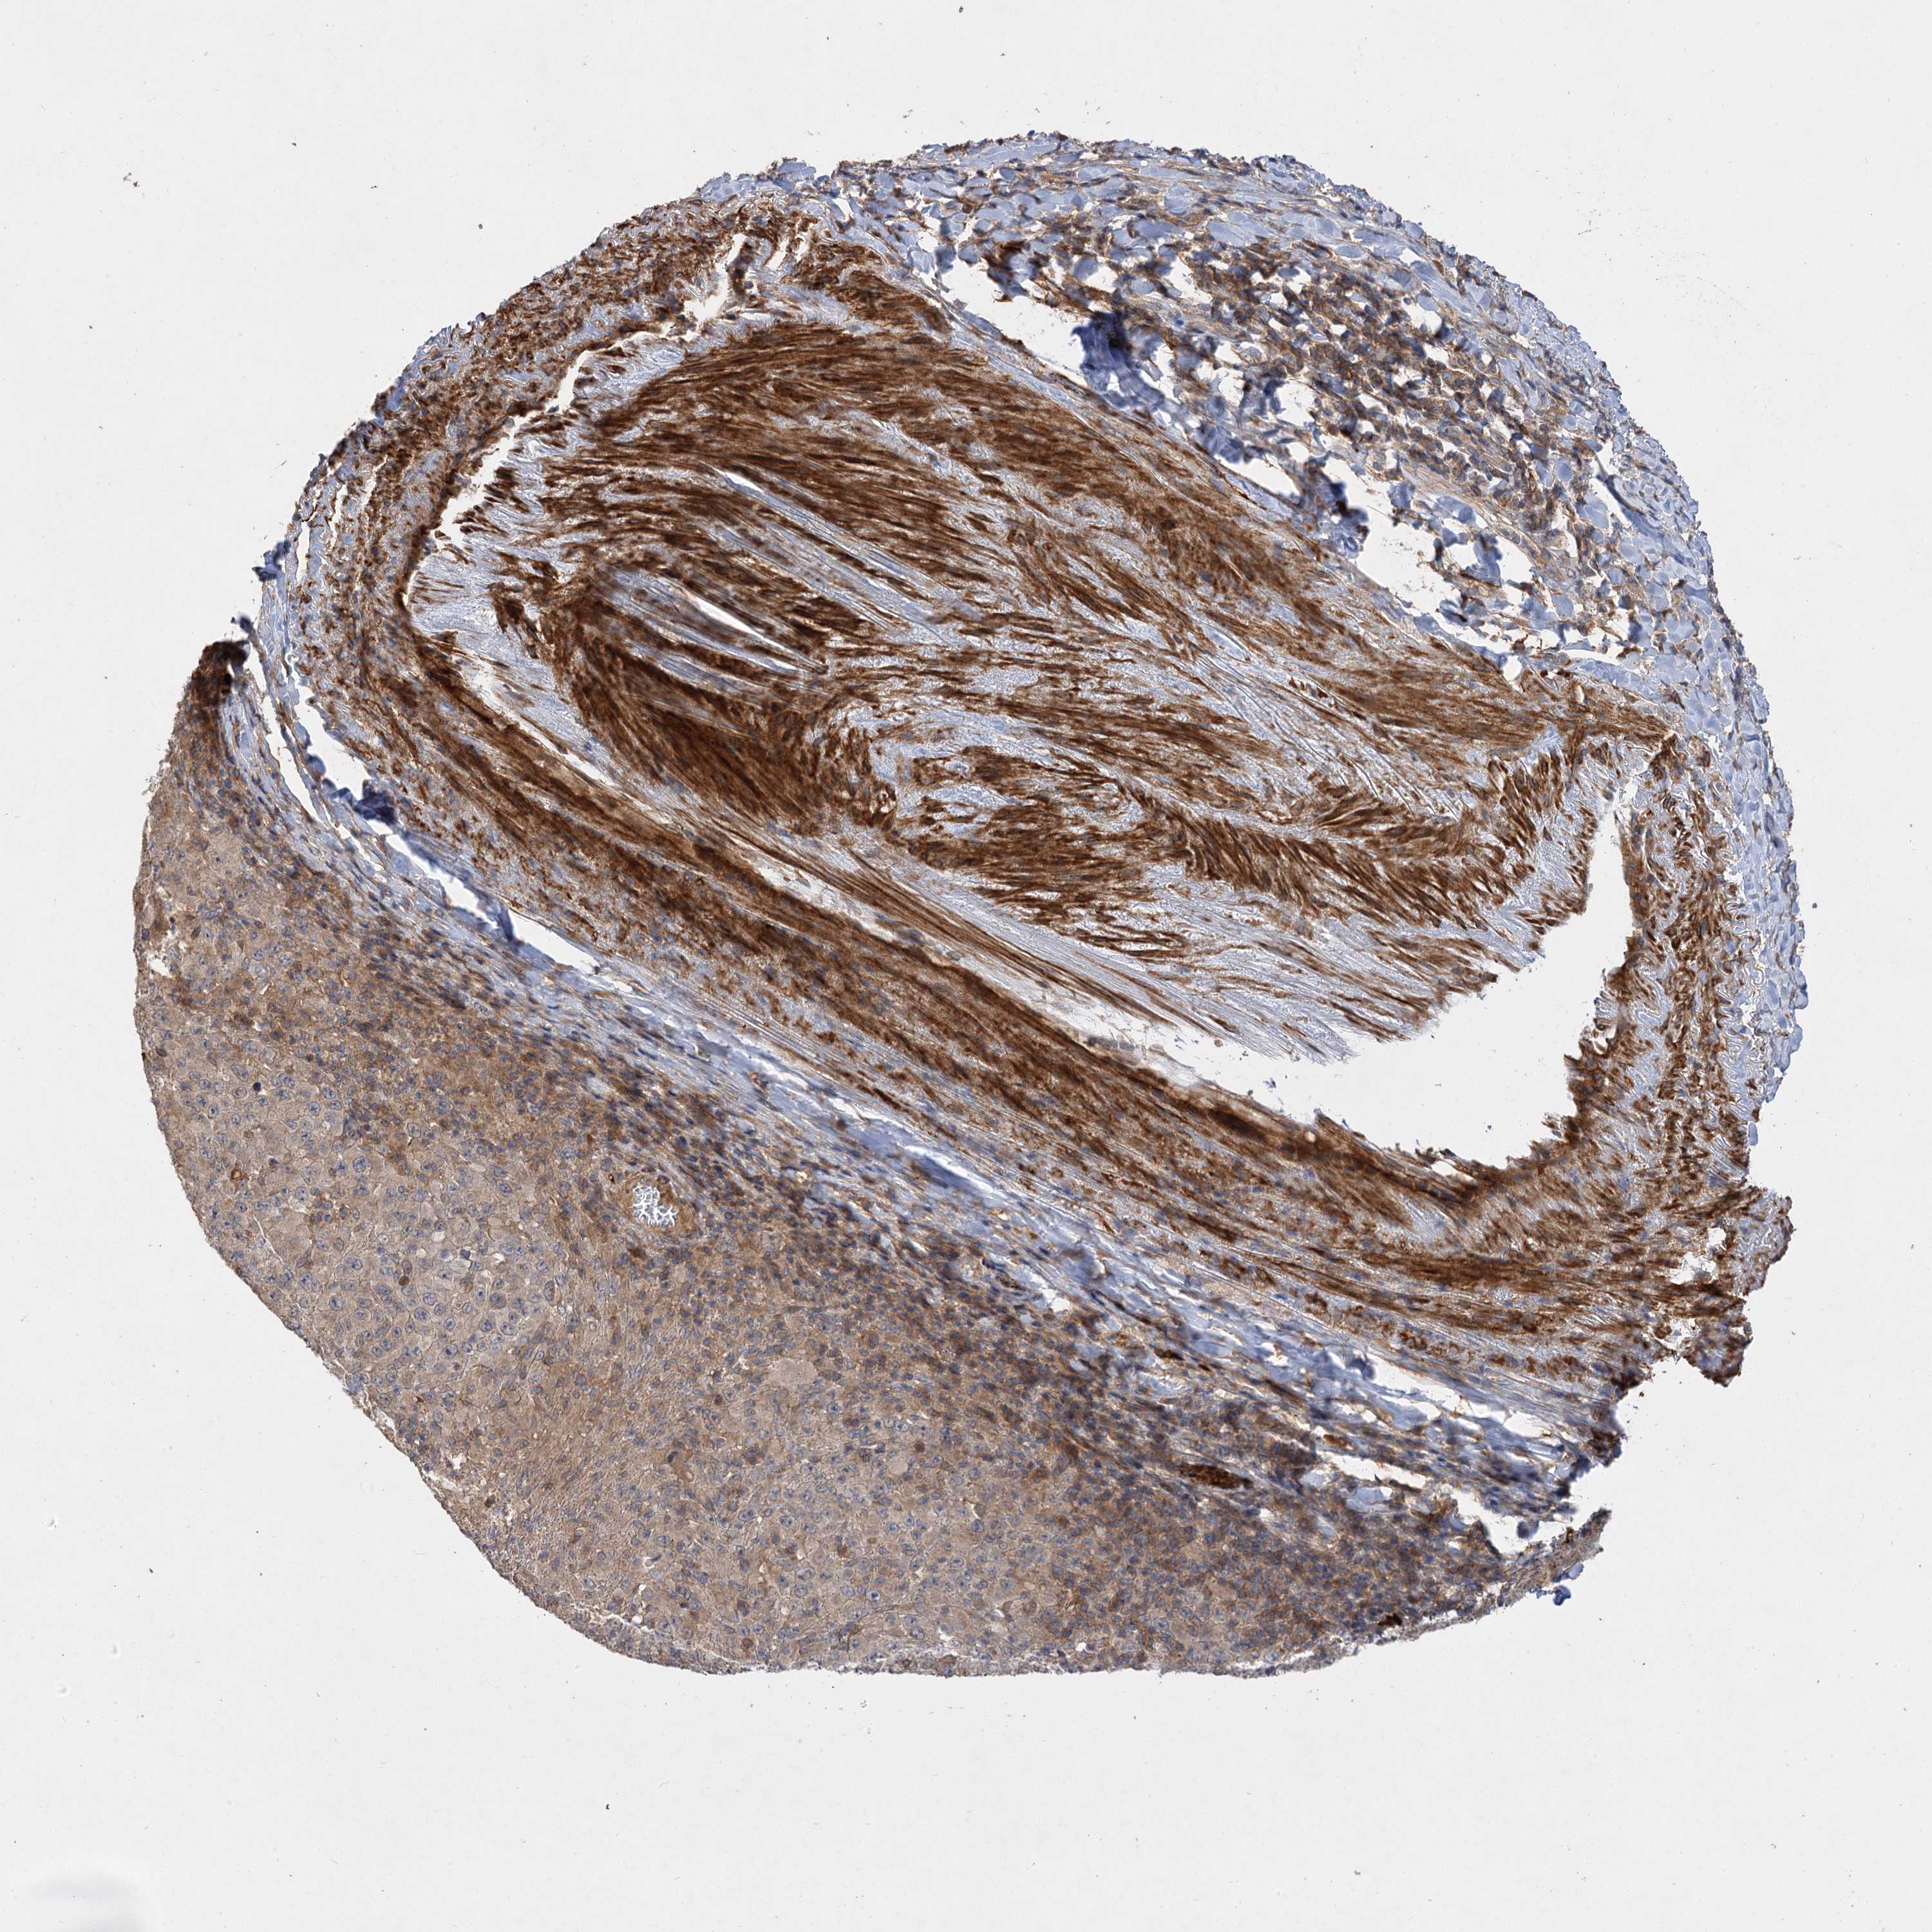

MELANOMA - Protein expressioni

A mouse-over function shows sample information and annotation data. Click on an image to view it in a full screen mode. Samples can be filtered based on level of antibody staining by selecting one or several of the following categories: high, medium, low and not detected. The assay and annotation is described here.

Note that samples used for immunohistochemistry by the Human Protein Atlas do not correspond to samples in the TCGA dataset.

Antibody stainingi

Antibody staining in the annotated cell types in the current human tissue is reported as not detected, low, medium, or high, based on conventional immunohistochemistry profiling in selected tissues. This score is based on the combination of the staining intensity and fraction of stained cells.

Each image is clickable and will lead to virtual microscopy that enables deeper exploration of all samples and also displays staining intensity scores, fraction scores and subcellular localization as well as patient and tissue information for each sample.

Antibody HPA038850

Antibody HPA038851

Malignant melanoma, NOS

Malignant melanoma, Metastatic site